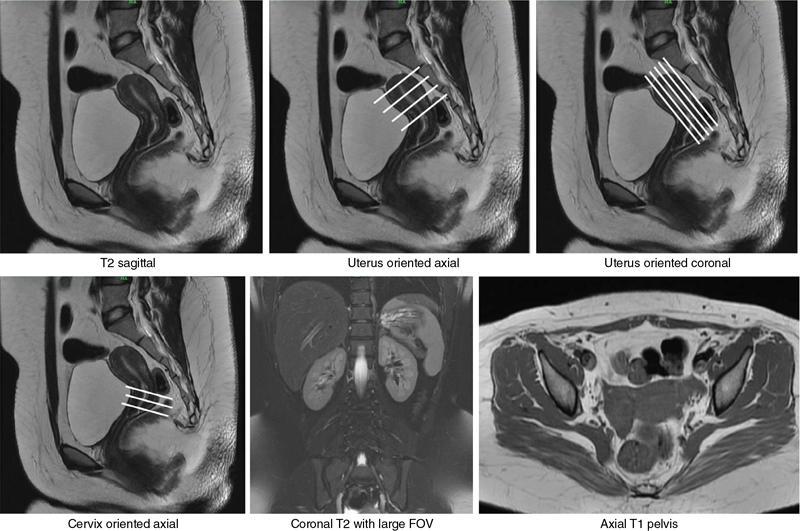

MÜLLERIAN DUCT ANOMALIES Rajani Gorantla Müllerian ducts are a pair of tubular structures that give rise to uterus, cervix, fallopian tubes and upper two-thirds of vagina. Disruption or failure of normal development can result in occurrence of Müllerian duct anomalies (MDAs). These are commonly associated with other congenital anomalies of urinary tract and ovaries due to the close relationship between the development of mesonephric and paramesonephric ducts; few patients also have associated skeletal system anomalies. The prevalence of MDAs in an unselected population was 5.5%; 8% among the infertile women, 12.3% in women with a history of recurrent pregnancy loss and 24.5% in women with miscarriage and infertility. Most of the patients with MDAs are asymptomatic and found incidentally on imaging for any other gynaecological problems, in evaluation of a patient with renal, skeletal or abdominal wall abnormalities. In symptomatic women, complains are related to the type, severity, obstructive anomaly or nonobstructive anomaly. The symptoms can be obstetric or gynaecological related, includes recurrent spontaneous abortions, infertility, preterm labour, intrauterine growth restriction and abnormal foetal lie. Few adolescent girls may present with primary amenorrhoea, hypomenorrhoea, abnormal vaginal bleeding, cyclical pain and mass. Rarely they can present with pelvic inflammatory disease with abnormal vaginal discharge, dyspareunia and urinary tract infections. The female reproductive system develops from a pair of Müllerian or paramesonephric ducts, urogenital sinus and vaginal plate. The ovaries develop separately from the primordial ridge. It is of great importance to understand the normal stages of development, as failure or interruption of any of these stages can lead to a simple to complex spectrum of anomalies. The three stages of Müllerian duct development include: At 6–10 weeks of gestation age, two paired Müllerian ducts and Wolffian ducts formation occurs. When Y chromosome factor (testicular determining factor) is absent, the Wolffian ducts undergo degeneration. The Müllerian ducts further elongate caudally and cross the Wolffian ducts to fuse in the midline. At 10–13 weeks of gestation age, caudal and lateral fusion of the two Müllerian ducts forms primitive uterovaginal canal, which is possessed of solid tissue initially located side by side and further internal canalization leads to the formation of two channels/canals divided by a septum. At this stage, there is reabsorption of the caudal septum and forms single cervical canal and vagina lumen. In around 15–20 weeks of gestation age, complete resorption of the septum takes place in a caudocranial direction from the isthmus to fundus and development of single endometrial cavity results. The fused caudal part of Müllerian ducts gives rise to the uterus, cervix and upper two-thirds of vagina; the unfused cranial part forms the fallopian tubes (Fig. 11.14.1.1). The lower vagina develops from the urogenital sinus, which is separated from the rectum by urorectal septum around 7 weeks of gestation age. The primitive uterovaginal canal embeds into the dorsal wall of urogenital sinus and forms Muller’s tubercle. Around 13 weeks of gestation, two solid masses known as sinovaginal bulbs originate from the upper part of the Muller’s tubercle, further proliferate into the caudal end of the uterovaginal canal to become a solid vaginal plate. Later canalization or degeneration of the central cells of the vaginal plate forms the lower vagina, which is usually completed by 20 weeks’ gestation. The vertical fusion of the upper and lower vagina occurs with resorption of tissue in between and forms single vaginal cavity (Fig. 11.14.1.2). The vaginal lumen is separated from the urogenital sinus by the hymenal membrane. Just before birth, the hymen normally ruptures due to retrogression of the central epithelial cells. However, a thin fold of mucous membrane persists around the vaginal introitus. The ovaries develop separately from migration of primordial germ cells to the genital ridge. Ureteric buds develop separately and concurrently. So renal anomalies are most commonly associated with MDAs with an association of 30%–50%. Various classification systems have been proposed over the past several decades to describe MDAs. Ideally, same classification system needs to be followed by a gynaecologist, surgeon and radiologist for better communication. Buttram and Gibbons classification was suggested in 1979, and it was based upon the level of failure in normal development and segregate the anomalies into groups with similar clinical manifestations, treatment, and prognosis for foetal salvage. According to Buttram and Gibbons, the uterine anomalies were classified into six classes as described in Table 11.14.1.1. The drawback is the lack of classification of vaginal and other anomalies separately. The ASRM (previously the American Fertility Society – AFS) classification system is the most widely accepted classification worldwide over the past years and was introduced in 1988. According to this classification, MDAs are classified into seven classes (class I to class VII) as mentioned in Table 11.14.1.2. However, several limitations have been described by Grimbizis and Campo in 2010 (Fig. 11.14.1.3). The drawbacks of the ASRM classification system are as follows: Hence in 2016, an updated classification of uterine septum, that is ASRM-2016 was proposed and officially approved morphometric criteria are given for distinguishing between septate, normal/arcuate and bicornuate uteri (Table 11.14.1.3). The VCUAM classification was proposed in the year 2005. The main concern is to provide a simple, systematic, clinical classification in addition to providing a precise reflection of the entire malformation. The female genital organs were divided into the following subgroups in accordance with the anatomy: vagina (V), cervix (C), uterus (U) and adnexa (A). Associated malformations were assigned to a subgroup (M) relative to each specific organ. The disadvantage is due to its inherent complexity, and more than 56,700 individual combinations of anomalies are possible. ESHRE and ESGE established a common working group named CONgenital UTerine Anomalies (CONUTA) in order to devise an improved classification system (Table 11.14.1.4). It was published in 2013. Anatomy is the basis for systemic categorization of the MDAs. The subclasses are divided by the different degrees of uterine deformity and their clinical significance (Fig. 11.14.1.4). Cervical and vaginal anomalies are classified into independent supplementary subclasses (Figs. 11.14.1.5–11.14.1.6). For most of the clinicians, it helped as starting point for the development of guidelines for their diagnosis and treatment. The malformations are graded according to severity, U0–U5, C0–C4 and V0–V4, with U5, C4 and V4 being more severe. Class U3 incorporates bicorporeal fusion defects (didelphys and bicornuate) as this was considered as a more functional mode of classification. Arcuate uterus was not included separately, but this is categorized under normal variant into class U1c. Recent studies have demonstrated that the ESHRE/ESGE system provides an effective and comprehensive classification for almost all the currently known MDAs and overcomes the limits of previous classifications. However, there is a relative overdiagnosis of septate uterus with the application of ESHRE–ESGE criteria has been reported and which potentially might lead to unnecessary surgical overtreatment. C0 C1 C2 Normal cervix Septate cervix Double ‘normal’ cervix C3 C4 Unilateral cervical aplasia Cervical aplasia U4 V0 V1 V2 V3 Normal vagina Longitudinal nonobstructing vaginal septum Longitudinal obstructing vaginal septum Transverse vaginal septum and/or imperforate hymen V4 Vaginal aplasia C MDAs’ characterization and classification is of great significance, as the treatment is determined by the type and severity of abnormality. The various imaging modalities available include: HSG was the most recognized imaging modality, earlier to the development of the ultrasonography (USG) and MRI. It is an invasive fluoroscopic-guided procedure for uterine and tubal assessment, and is performed during the midproliferative phase of the cycle, ideally between days 7 and 10 of the cycle when endometrium is thin. Fluoroscopic spot images obtained to evaluate uterine configuration, uterine filling defects and fallopian tube patency. HSG allows evaluation of only the component of the uterine cavity that communicates with the cervix. The anatomic information about myometrium and external fundal contour will not be provided by HSG. The diagnostic criteria used to diagnose MDAs on HSG include: HSG findings of different MDAs are described in Table 11.14.1.5 and Fig. 11.14.1.10. Virtual HSG is a noninvasive technique performed by using a computed tomography (CT) scanner, done 45 s after the contrast material instillation begins. Contraindications are similar to those for HSG and include pregnancy and active pelvic infection. There is no necessity for retraction of the uterus or manipulation of the cervix. The procedure is quick, easy and prophylactic administration of antibiotics is not required. The use of a power injector helps to ensure a steady low pressure of instillation. The procedure is less painful, more comfortable and easily tolerated by patients than conventional HSG. Radiation exposure sometimes requires cervical clamping, which may result in complications such as bleeding and infection. Transabdominal pelvic ultrasound can diagnose uterine anomalies with accuracy rate of 47%. Two-dimensional transvaginal ultrasound (TVUS) has high sensitivity and specificity than transabdominal study and provided some information about external and internal fundal contours. The detection rate is high if the scan is performed in secretory phase due to better visualization of endometrium. Three-dimensional USG shows great accuracy than 2D USG in evaluation of the uterine morphology. The technique of 3D USG varies with different vendors. It displays both the external and internal fundal contours and lower uterine segment by acquisition of single coronal view of uterus (c-view) (Fig. 11.14.1.11). The only disadvantage is that it is transvaginal study and shall not be done in paediatric age group and sexually inactive women. Three-dimensional TVUS has become the first line of screening tool in most of the infertility clinics as it is noninvasive, faster, repeatable, allows storage of volume data and has multiplanar capability for systematic evaluation of the uterine and cervical cavities. The salient features of various Müllerian anomalies on 3D USG are described in Table 11.14.1.6 with images. Three-dimensional ultrasound is combined with sonosalpingography in this technique and provides better delineation of the uterine morphology. It is a less invasive procedure done in proliferative phase with instillation of saline into the uterine cavity and assessment of the uterus will be done. MRI is a universally accepted imaging modality in the documentation of MDAs and accuracy rate of 100% have been reported. MRI provides excellent delineation of both the internal and external uterine anatomies. T2-weighted (T2W) images are the mainstay of pelvic imaging and are performed without fat suppression. T1-weighted (T1W) images are mainly for the haemorrhagic content. The disadvantages of MRI include time-consuming procedure, not cost-effective, large body habitus, pacemakers, recent surgical history and claustrophobia. The current and proposed MRI protocol given by the European Society of Urology (ESUR-MRI protocol) intends a dedicated evaluation of MDAs as mentioned below (Fig. 11.14.1.12): Vaginal anomalies can be accurately diagnosed with the prior administration of the ultrasound gel, to distend vagina (Fig. 11.14.1.13). It will help in better diagnosis of complex vaginal anomalies, like vaginal septations or vaginal duplication. The normal MRI appearance of uterocervical canal and vagina are shown in Fig. 11.14.1.14. Uterine aplasia/hypoplasia/agenesis is class 1 MDA according to ASRM classification and U5 uterine anomaly according to ESHRE classification. It is a formation defect of the paramesonephric ducts with complete or segmental agenesis of uterus and vagina. The incidence rate is around 10%–15% of all MDAs and considered as the most severe form of uterine anomaly. Most of them have complete uterovaginal agenesis with no single completely developed uterine cavity and are associated with Mayer–Rokitansky–Küster–Hauser syndrome (MRKHS). Two types of this syndrome are depicted. The typical form or type A represents the absence or remnants of the uterus, cervix, upper two-thirds of vagina with normal ovaries and fallopian tube (Fig. 11.14.1.15). The atypical form or type B is associated with the abnormalities of the ovaries, fallopian tubes and genitourinary system (Fig. 11.14.1.16). In a few cases (approximately 10%), unilateral or bilateral uterine remnants and with or without endometrial cavity will be seen (Fig. 11.14.1.17). Most of them present with primary amenorrhoea due to complete uterovaginal agenesis and manifest as MRKHS. These patients have normal secondary sexual characteristics due to the preserved normal ovarian function and phenotype. If uterine remnants with functional cavity is present, will present with cyclical pain along with amenorrhoea due to cryptomenorrhoea and haematometra. USG is the first modality for identification of these anomalies, absence of uterus with normal ovaries is diagnostic. But, it is difficult to locate the uterine remnants and cavity due to small acoustic window. MRI is the gold standard and it classifies into uterovaginal agenesis and hypoplasia. If hypoplasia is identified, sagittal and axial sections are taken. These remnants are seen as T2 hypointense tubular structures, located in close relation to ovaries in the adnexa. Once we identify the uterine remnants, it is important to look for the functional endometrial cavity. These will have reduced endometrial and myometrial width. MRI can easily delineate the zonal anatomy due to its high soft tissue contrast resolution. The management of Müllerian agenesis consists of counselling for the patient and her parents. Some patients with MRKHS opt for creation of neovagina for normal sexual life. Various techniques are available. In the presence of a functional Müllerian remnant, regardless of whether it is communicating or not, medical suppression of menses can be initiated and should be followed by laparoscopic removal of the hypoplastic remnant. Unicornuate uterus or hemiuterus is defined as the unilateral uterine development and the contralateral Müllerian duct could be either partially formed or absent. It is a formation defect and the necessity to classify it in a different class than that of uterine agenesis, which is also a formation defect, is due to the existence of a fully developed functional uterine hemicavity. It is considered as class II anomaly according to ASRM classification and class U4 according to ESHRE classification. The frequency rate is around 20% of MDAs. Renal anomalies most often occur in association with unicornuate uterus and usually on the same side of uterine agenesis. Further unicornuate uterus is divided into two subclasses depending on the presence or absence of a functional rudimentary cavity in ESHRE classification: In ASRM classification, unicornuate uterus is divided into four subcategories: Mostly asymptomatic and presence of the noncommunicating uterine remnants will be identified at the time of infertility work up or caesarean section. If a functional cavity is present, the presentation is dysmenorrhoea or haematometra in an adolescent. The common obstetrics-related complications include abnormal foetal lie, intrauterine growth retardation, preterm delivery, placental abnormalities and uterine rupture. Gynaecological complications are ectopic pregnancy and endometriosis due to retrograde menstruation. On imaging, unicornuate uterus is seen as tubular and fusiform or banana-shaped structure at paramedian location, the endometrium is narrow and tapers to the apex with normal myometrial anatomy and reduced uterine volume. The rudimentary cavity or remnants are better depicted on 3D USG (Fig. 11.14.1.18) and MRI. However, MRI is superior to USG due to its high soft tissue resolution. The rudimentary cavity can communicate with main cavity or connected by fibrous band. The nonfunctioning cavity will be seen as T2 hypointense structure with loss of zonal anatomy (Figs 11.14.1.19 and 11.14.1.20), whereas the functioning cavity will show the deformed zonal anatomy (Fig. 11.14.1.21), and its complications like haematometra as T1/T2 hyperintense endometrial collection. Unicornuate uterus without rudimentary cavity does not require any procedure. But in the presence of communicating or noncommunicating rudimentary horn, surgical resection must be considered to prevent complications. Uterine didelphys is a class III MDA based on the ASRM classification and class U3b bicorporeal uterus according to ESHRE classification with an incidence rate of 5% among the uterine anomalies. It is a lateral fusion defect; results from complete failure of the Müllerian duct fusion. Two noncommunicating endometrial cavities with preserved zonal anatomy are seen with separate cervix. According to ESHRE classification, it is defined as external fundal indentation completely dividing the uterine corpus up to the level of external cervical os. It is most commonly associated with longitudinal vaginal septum in around 75% of cases. Some patients may show transverse vaginal septum and these will be obstructive or nonobstructive type. Renal anomalies are also commonly associated with uterine didelphys. Uterine didelphys is usually asymptomatic and diagnosed incidentally on pelvic examination or caesarean section. The uterine didelphys with obstructed vagina (Fig. 11.14.1.22) will present at adolescence as dysmenorrhoea, haematometrocolpos and haematosalpinx. Sometimes retrograde menstrual flow can cause endometriosis and pelvic adhesions. Obstetric-related complications include abortion/foetal growth restriction and poor pregnancy outcome. The uterine didelphys with obstructed hemivagina due to transverse vaginal septum and associated ipsilateral renal agenesis are the manifestations of the syndrome called obstructed hemivagina and ipsilateral renal agenesis anomaly/Herlyn–Werner–Wunderlich (HWW) syndrome (Fig. 11.14.1.23).